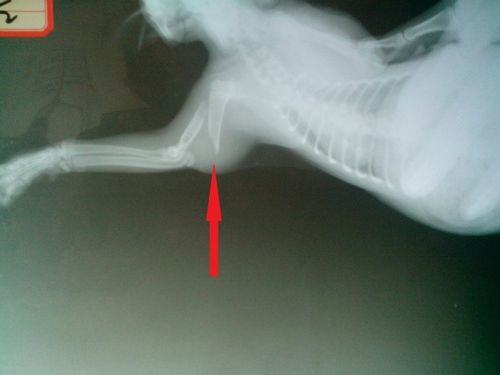

下面介绍病例,患猫名字:小M,品种:美国短毛猫,年龄:三月龄,因玩耍从楼上摔下遂送来医院救治,并未出现内出血等情况,生理以及生化指标均正常。拍摄X光后发现全身三处骨折,分别是左侧肱骨骨折,右侧后肢股骨近端骨折和左侧髋臼窝骨折。下图为猫的骨骼解剖图,红色箭头所示的就是肱骨的位置。

图为猫骨骼示意图,猫的肱骨的位置位于前肢,属于上肢骨

箭头指示的就是断裂的肱骨,属于典型斜骨折,周围组织由于断骨的错位而肿胀